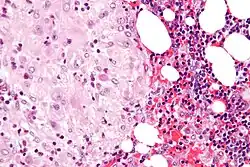

Acute choriodeciduitis, with neutrophils seen in the chorion and decidua.

The decidua has a histologically-distinct appearance, displaying large polygonal decidual cells in the stroma. These are enlarged endometrial stromal cells, which resemble epithelium (and are referred to as "epithelioid").

Its leukocyte population is distinct, with the presence of large endometrial granular leukocytes being predominant, while polynuclear leukocytes and B cells are scant.